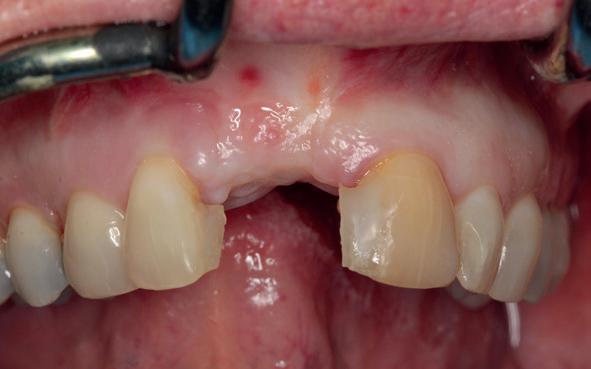

Er werd meer bekend over de gedragingen van het bot rond de “microgap” en daarmee kwam er meer begrip over hoe een implantaat goed te plaatsen in de esthetische zone. In het midden van de jaren negentig kwam daar de kennis bij hoe, op een verantwoorde manier en met behulp van guided-bone-regeneration, een implantaat in de esthetische zone te plaatsen (afbeelding 6-10).

Van vooral functionaliteit verschoof de indicatie naar esthetiek. De zachteweefselchirurgie en vaak voorbehandeling van zachte weefsels voor implantologie kreeg veel meer aandacht (afbeelding 11-14).